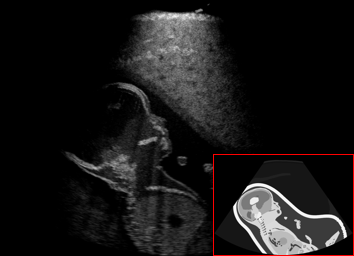

US simulation. We used a ray-tracing framework to render B-mode images from a geometric fetal model, by simulating a convex probe placed at multiple locations and orientations on the abdominal surface, with imaging settings listed in Tab 1. At each location, simply rasterizing a cross-section through the triangulated anatomical surfaces at the ultrasound center imaging plane provided corresponding semantic maps. Fig. 3 shows example B-mode images with corresponding semantic maps. A total of simulated frames were resized to and randomly split into training-validation-test sets by 80-10-10%.

In Fig. 3 we show that only learning an auxiliary seg-to-real translation, i.e. CUT+S, cannot guide the network to learn the semantics of simulated images.

CUT+SC with the loss term largely reduces hallucinated image content, although it still fails to generate fine anatomical details. With the multi-domain conditional generator and additional losses of ConPres, translated images preserve content and feature a realistic appearance. Training without leads to training instability.

Comparison to state-of-the-art. As seen qualitatively from the examples in Fig. 3, our method substantially outperforms the alternatives in terms of content preservation, while translating realistic US appearance. CycleGAN, SASAN, and CUT hallucinate inexistent tissue regions fail to generate fine anatomical structures, e.g. the ribs. StarGAN fails to generate faithful ultrasound speckle appearance, which leads to highly unrealistic images. Our method ConPres preserves anatomical structures, while enhancing the images with a realistic appearance. It further faithfully preserves acoustic shadows, even without explicit enforcement. However, as seen from the last column, the refraction artefact appears artificial in the images translated by all the methods. Note that although the imaging field-of-view (FoV) and probe opening in the simulation is significantly different from the real in-vivo images (Fig. 2) used for training, our ConPres maintains the input FoV closely compared to previous state-of-the-art. The results in Tab 2 quantitatively confirm the superiority of our method. Note that SSIM and FID/KID are used to measure translation performance from two different and sometimes competing aspects, with the former metric for quantifying structure preservation and the latter metrics for image realism.